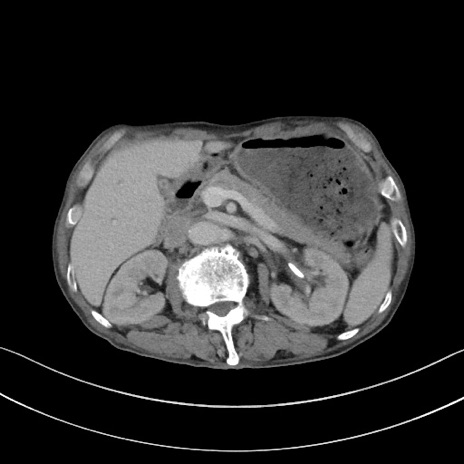

症例3(横断像)

【症例】 70歳代男性

【主訴】右鼠径部腫瘤、疼痛

【現病歴】本日朝より上記主訴あり、受診。

【既往歴】膀胱癌にて膀胱全摘、両側尿管皮膚瘻

【データ】WBC 5600、CRP 0.56